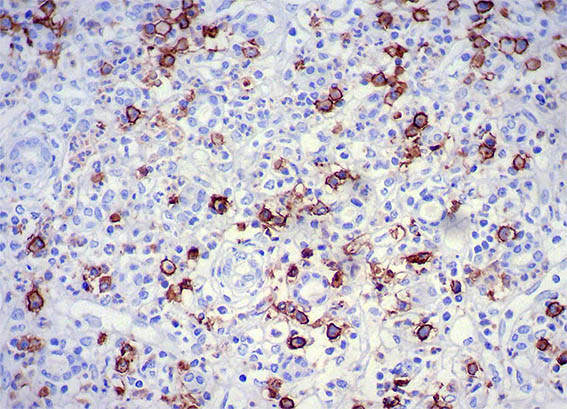

Figure 10. Immunohistochemistry for IgG, X400.

Figure 11. Immunohistochemistry for IgG4, X200.